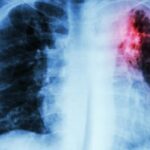

La intoxicación por bloqueadores beta-adrenérgicos es un fenómeno clínico complejo que se asocia a la administración excesiva o inadecuada de fármacos que actúan sobre los receptores beta-adrenérgicos del sistema nervioso…